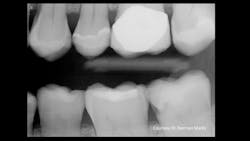

Recently, one of our practicing dentist team members who donates significant time to Clinicians Report Foundation and Practical Clinical Courses sent me a clinical example that frustrated both of us (figures 1 and 2). As you observe Figure 1, you will immediately see a lesion on the mandibular second molar and—perhaps—a small lesion on the maxillary first premolar. But do you see the lesion on the maxillary second molar? As you observe Figure 2, you are shocked to see the depth of the MO lesion that was not visible on the radiograph.

Figure 2: Obviously, the radiograph in Figure 1 did not show the major carious lesion.